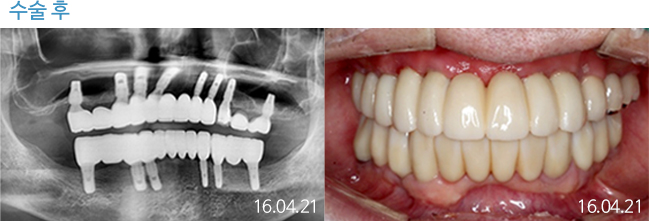

한 번 잘 심으면 10년 뒤에도 끄떡없는

더와이즈 임플란트

첨단 장비를 이용한 정확한 진단, 안정성이 입증된 정품 재료 사용,

노하우가 풍부한 숙련된 의료진의 시술 등이 임플란트 수명을 결정합니다.

※ 실제 본원에서 치료 받은 환자의 동의를 얻어 게재했습니다.

개인의 특성에 따라 부작용이 발생할 수 있으므로 담당의와 충분히 상의하시길 바랍니다.